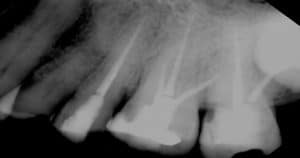

- Füllung – die Kanäle werden dicht verschlossen, damit keine neuen Keime eindringen.